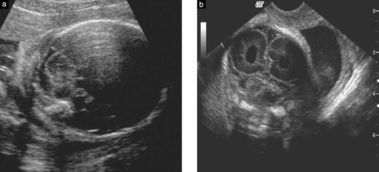

如果怀孕的母亲担心胎儿的健康问题,可以先去医院进行产前检查。医生会采用超声波等技术观察胎儿的发育情况并对胎儿小脑偏小进行诊断。在孕期结束时,医生还会进行一次全面的检查。如果检查结果显示胎儿小脑偏小,需要立即采取行动,以尽可能地避免对新生儿的健康产生不利影响。